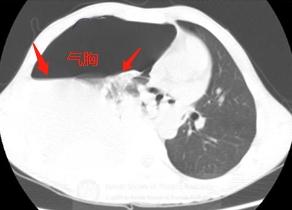

打喷嚏后出现右边胸口疼,呼吸困难,不能深吸气,赶紧上担架车做了急诊CT:

胸部CT显示右侧液气胸,胸腔积液和气体压迫肺组织,导致呼吸困难和不能深吸气,并且挤压心脏向左侧移位。

再看纵隔窗:

在大量灰色的胸水里,有一块椭圆形的小团块沉在水底,里面还有4个小气泡。

这个病人不是单纯的液气胸,准确点说,他是自发性血气胸,出血量在400ml以上了。